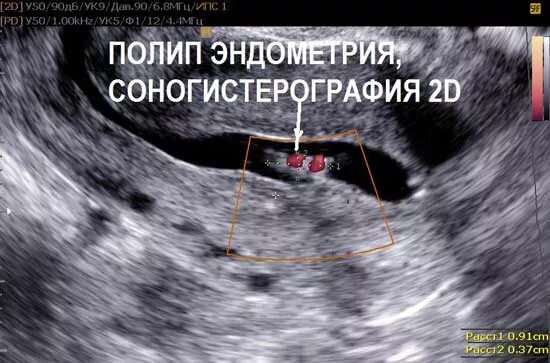

Эндометрий 9 мм